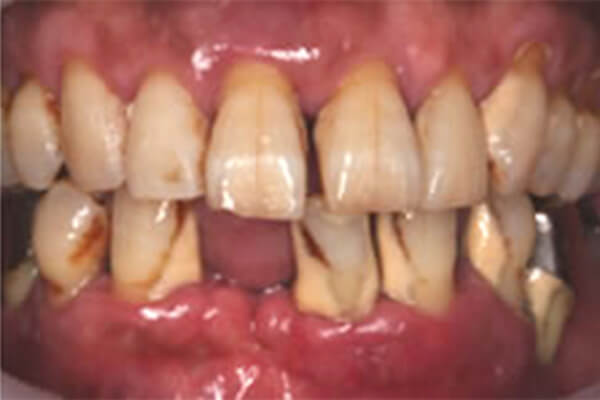

他院で定期検診を受けていましたが、近い将来入れ⻭になることを言われ不安になり、当院に来られました。全体的に⻭周病は重度に進行し、⻭の動揺や⻭の病的移動を認め⻭並びが悪く、うまく咬めていませんでした。

初診時の状態

(口腔内写真とデンタルX線)

症例 症例

全体的に⻭茎は腫れ、⻭を支える骨がかなり溶けて⻭茎も下がっています。重度に⻭周病が進行すると⻭が病的移動を起こし、⻭並びも悪くなり噛み合わせに異常が生じています。